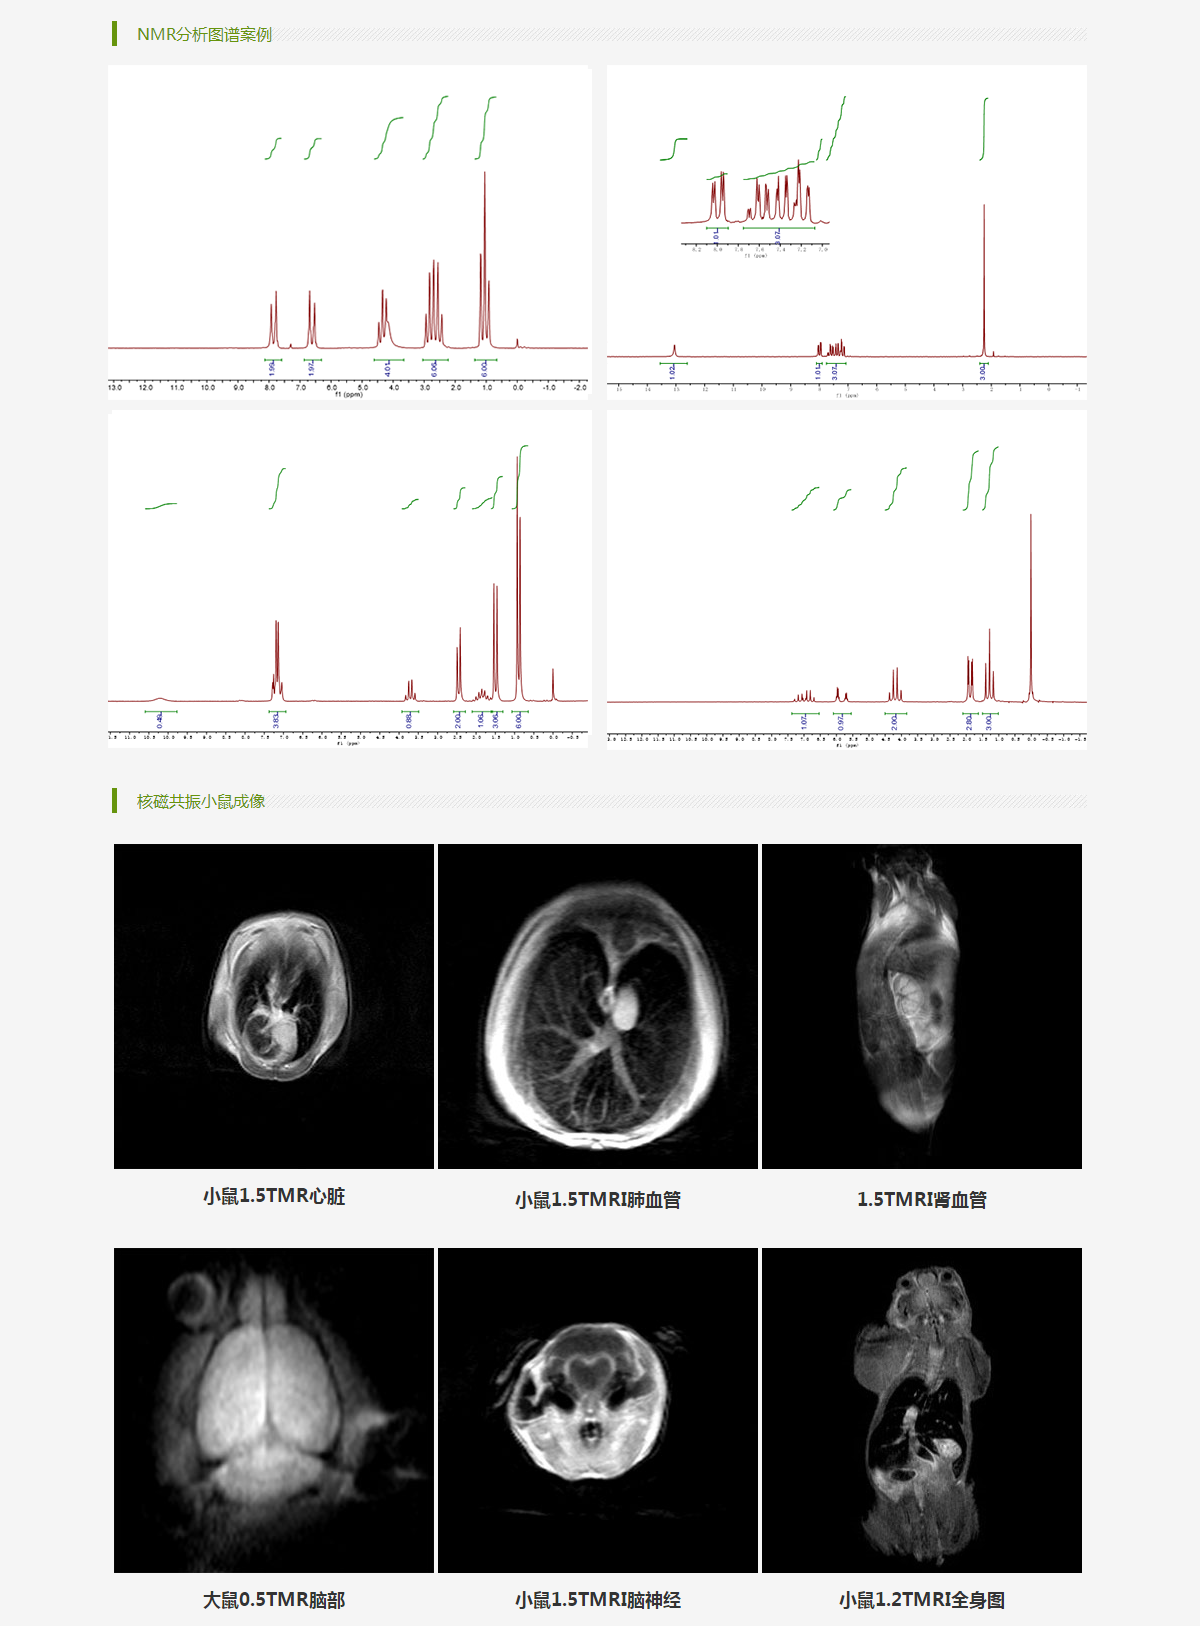

小动物核磁共振成像系列

核磁共振波谱分析系列

核磁共振成像分析应用系列

上海寰彤科教设备有限公司主要专注于核磁共振成像技术以及NMR分析技术的创新和研发,是一家集测试、研发、生产、销售、服务为一体的磁共振产品制造企业。公司的产品广泛应用于医学影像、药物分析、生物医药等多个科研、教学领域,覆盖核磁共振波谱高分辨化学分析、磁共振成像等技术范畴,并拥有自主国产化的生产能力与独立的研发设计能力。

公司致力于医学成像类、核磁共振波谱分析设备制造研发,产品涵盖NMR、MR、成像类、波谱类设备,应用于生物、药物、材料,食品,化学等领域。目前已有永磁60/90MHz核磁共振波谱仪,永磁(1.5T)H/F/P多核小动物核磁共振成像与弛豫测量系统,低场核磁共振分析系统,清醒小动物体成分检测仪等多种科研分析产品。